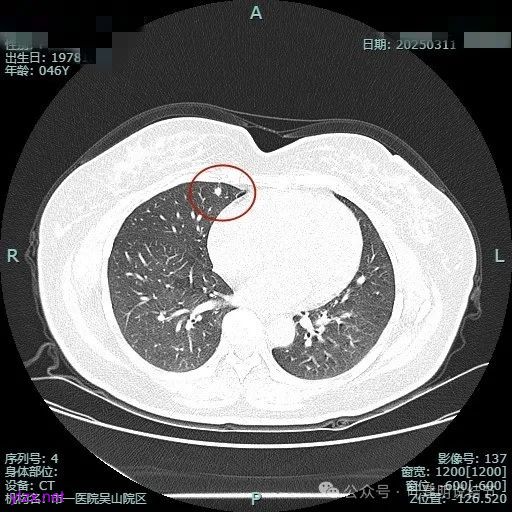

病灶1:

病灶是混合密度,边缘少许淡磨玻璃,灶内不太致密,表面不平,血管征有,但说不上明显异常增粗。

病灶紧贴叶间裂,而且感觉跨过肺叶,部分影响到上叶了,病灶本身密度虽实性为主,但是不太致密,有点松散的感觉。

总体实性部分密度较高,而磨玻璃部分密度较低,且瘤肺边界欠清,关键是跨叶间裂生长,这与肿瘤似乎不容易解释些。

毛刺有但不太锐利,磨玻璃有但偏淡,实性为但不太致密,叶间裂与之关系密切,病灶跨叶生长。

上图显得与肿瘤较为符合,但跨叶生长的话,侵袭力应该较强,可她这病灶较刚发现时进展并不太明显。

上图层面也较符合恶性,血管进入明显,有浅分叶的样子,整体觉得有一定收缩力与膨胀感。

病灶表面不平,混合密度,磨玻璃成分较淡。